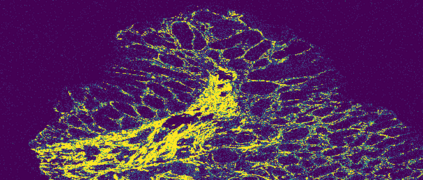

The usage of chemical imaging technologies is becoming a routine accompaniment to traditional methods in pathology. Significant technological advances have developed these next generation techniques to provide rich, spatially resolved, multidimensional chemical images. The rise of digital pathology has significantly enhanced the synergy of these imaging modalities with optical microscopy and immunohistochemistry, enhancing our understanding of the biological mechanisms and progression of diseases. Techniques such as imaging mass cytometry provide labelled multidimensional (multiplex) images of specific components used in conjunction with digital pathology techniques. These powerful techniques generate a wealth of high dimensional data that create significant challenges in data analysis. Unsupervised methods such as clustering are an attractive way to analyse these data, however, they require the selection of parameters such as the number of clusters. Here we propose a methodology to estimate the number of clusters in an automatic data-driven manner using a deep sparse autoencoder to embed the data into a lower dimensional space. We compute the density of regions in the embedded space, the majority of which are empty, enabling the high density regions to be detected as outliers and provide an estimate for the number of clusters. This framework provides a fully unsupervised and data-driven method to analyse multidimensional data. In this work we demonstrate our method using 45 multiplex imaging mass cytometry datasets. Moreover, our model is trained using only one of the datasets and the learned embedding is applied to the remaining 44 images providing an efficient process for data analysis. Finally, we demonstrate the high computational efficiency of our method which is two orders of magnitude faster than estimating via computing the sum squared distances as a function of cluster number.